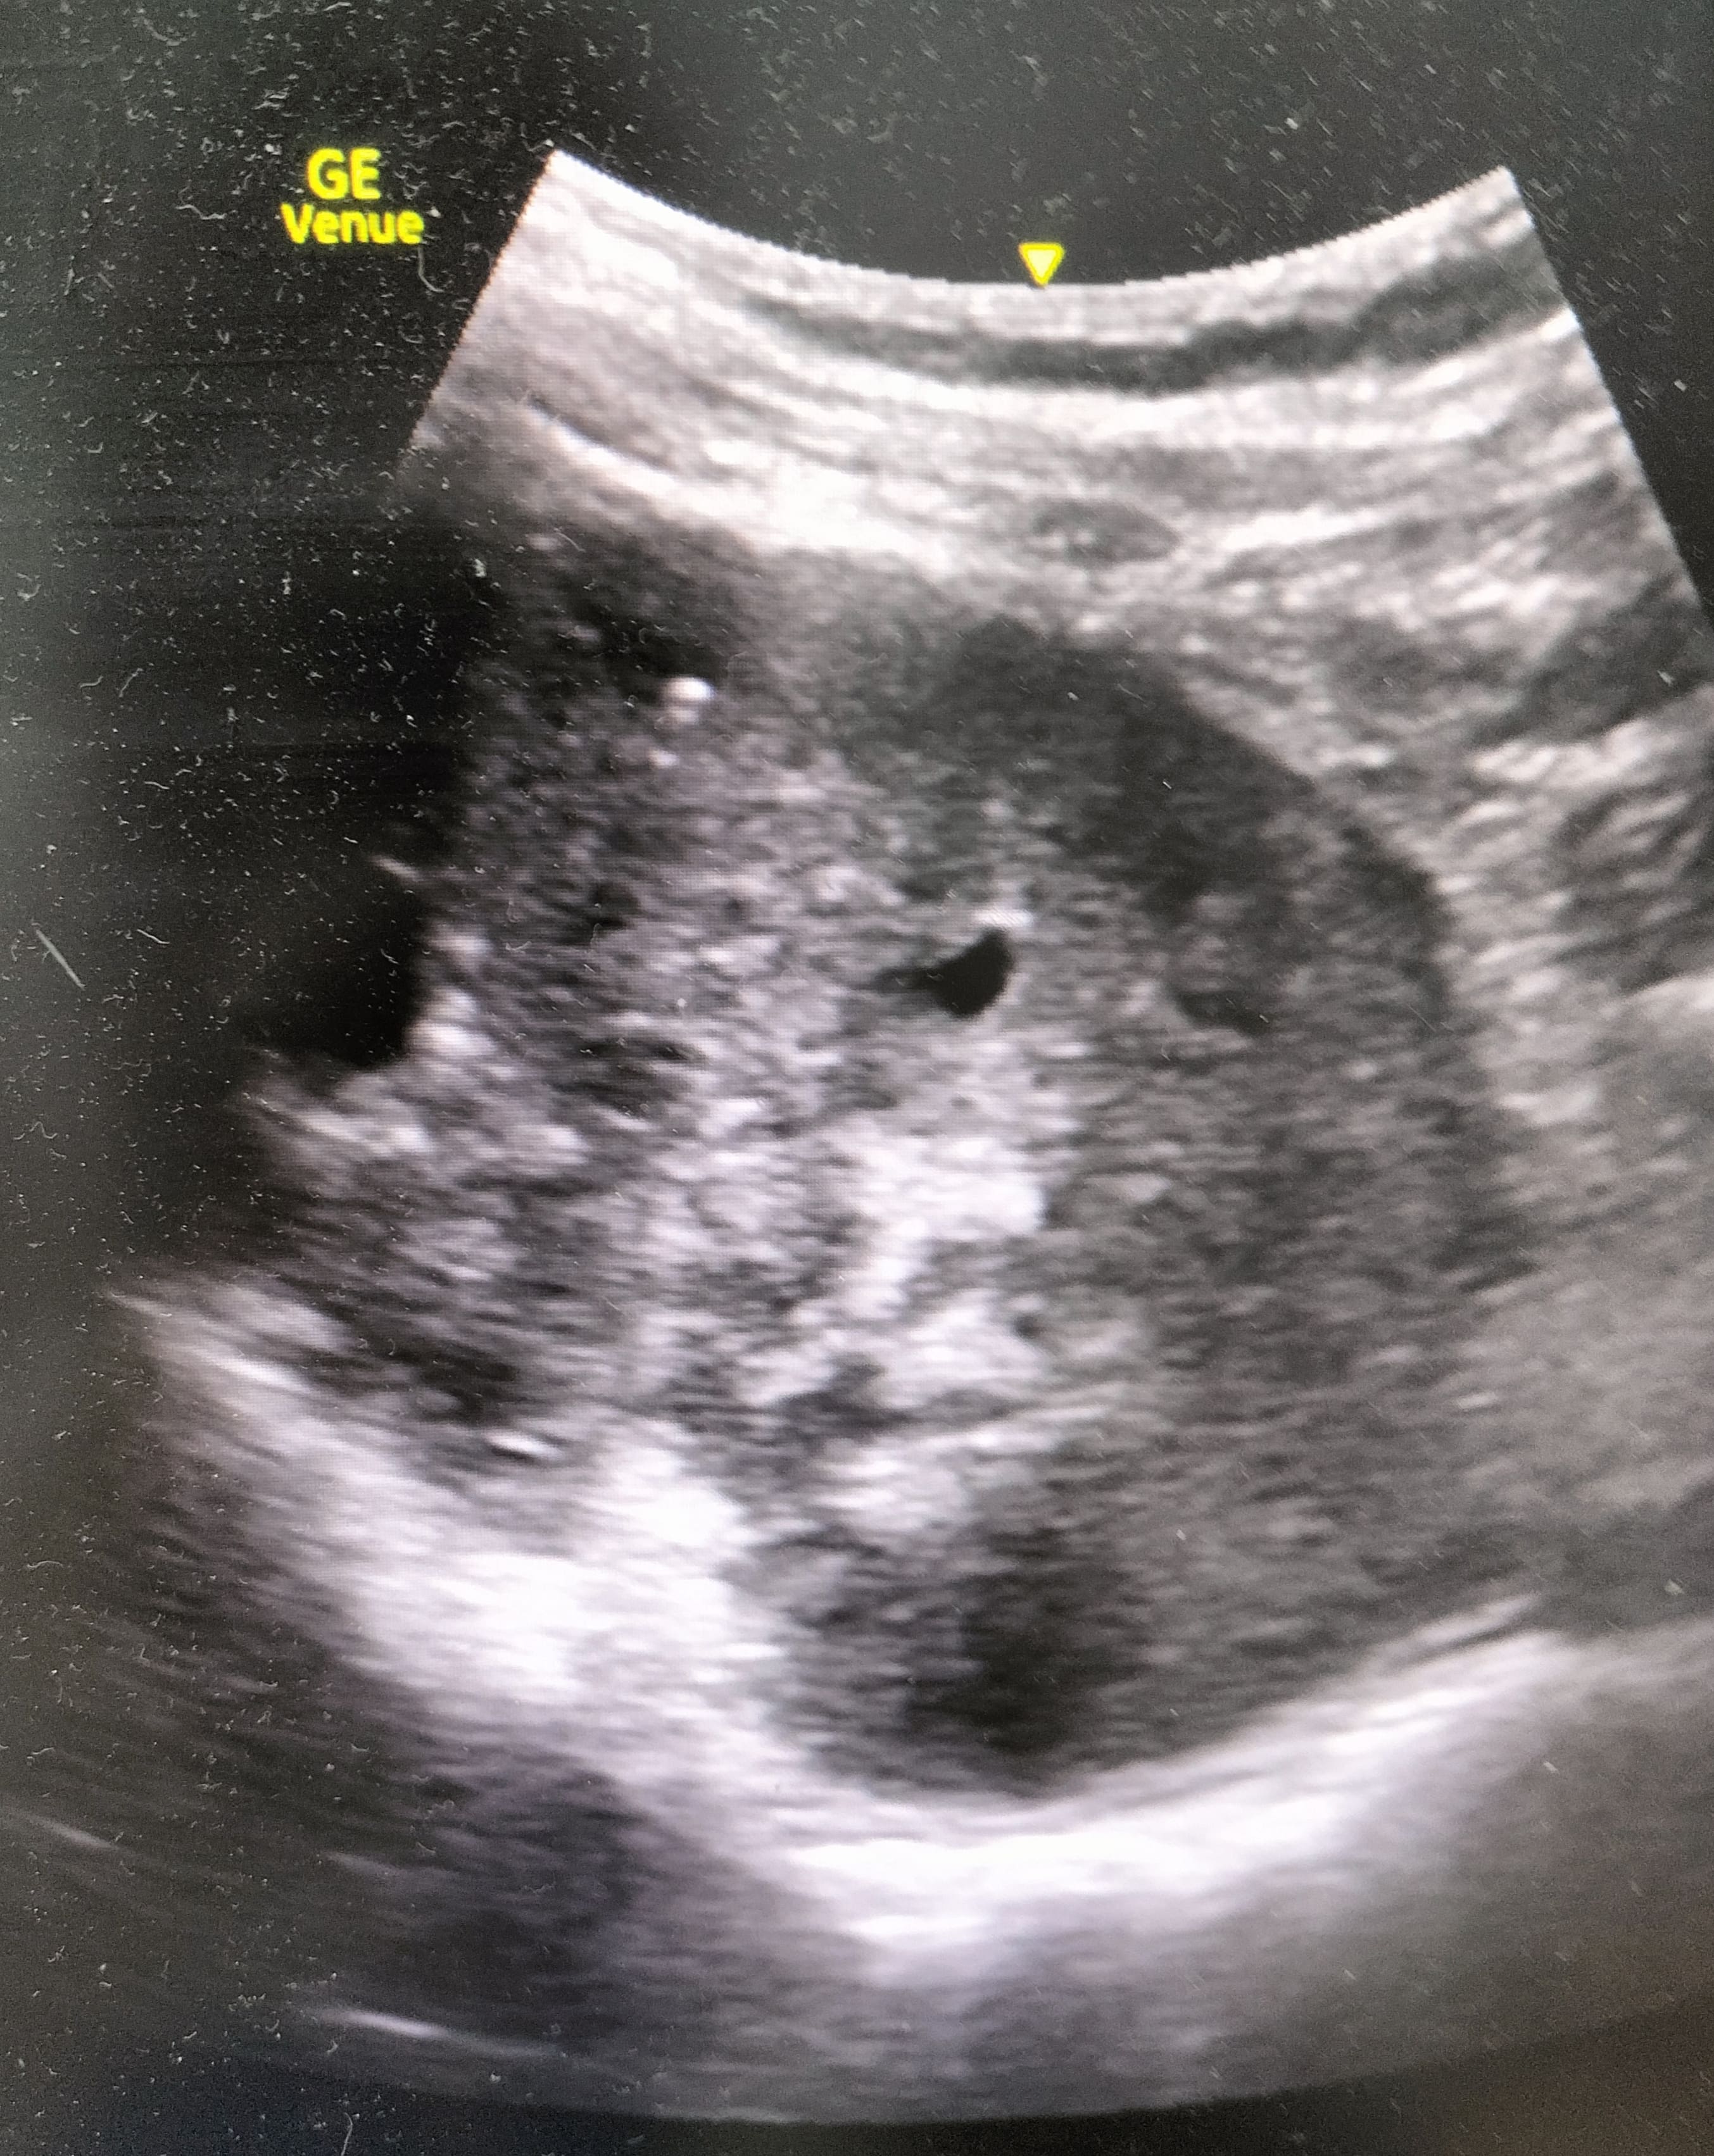

La realización de la técnica muestra riñón derecho aumentado de tamaño y una imagen compatible con una masa renal derecha con pérdida de la diferenciación cortico-medular. En contraposición se observa una silueta renal contralateral sin alteraciones.

En la analítica sanguínea se destaca deterioro de la función renal y la analítica de orina señala la presencia de hematuria. Se comenta el paciente con el Servicio de Radiología y se consensúa realización de TAC tóraco-abdominal, donde se objetiva una neoplasia renal derecha que infiltra arteria y venas principales, con trombosis de la cava desde el hilio renal hasta la porción intrahepática así como adenopatías retroperitoneales.